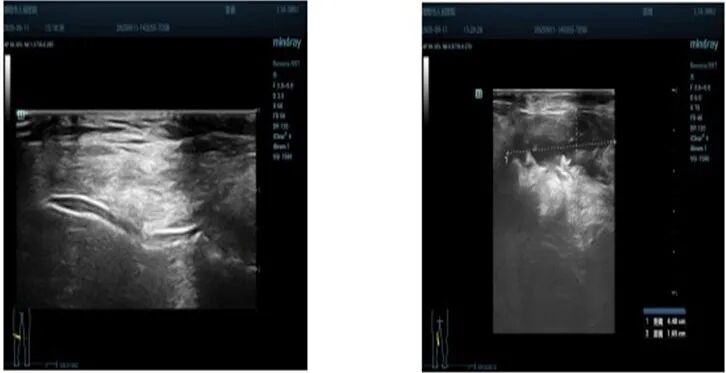

浅表彩超(腕关节):右腕伸肌腱、屈肌腱肌腱内及腱鞘强回声团(痛风石?)双腕点状强回声(尿酸盐沉积?)(图3)。

图3. 膝关节浅表彩超

浅表彩超(膝关节):双膝股四头肌肌腱水肿,内可见强回声团。双膝髌上囊可见少量积液及少量滑膜增生并可见多个强回声团。双膝髁间软骨可见双轨征。双膝腘窝查见囊性暗区,壁厚,内不清晰,内可见强回声沉积。右侧大小约5.0X1.6cm,左侧大小约4.5×1.7cm(图4)。

图4. 膝关节浅表彩超

本病例为风湿免疫科医师处理复杂共病痛风患者提供了极具价值的范本。它深刻说明,面对高龄、心肾功能不全、出血风险等多重限制时,基于疾病核心机制(IL-1β通路)的靶向治疗,能够实现“鱼与熊掌兼得”——即强效抗炎与良好安全性的平衡。超声影像显示的多发肌腱内强回声团(痛风石?)及关节内尿酸盐沉积,也提示此类患者往往存在严重的慢性晶体负荷,急性期炎症的彻底控制是后续一切治疗(包括降尿酸、甚至手术清创)的前提。未来,随着对痛风炎症通路认识的深化及更多靶向药物的可及,个体化、精准化的急性期治疗方案将更加丰富。对于类似本例的高危患者,早期评估并适时启用IL-1β抑制剂,或许能更主动地避免激素依赖、减少并发症、保护靶器官功能,从而真正改善患者的长期预后与生活质量。此案例不仅是一次成功的治疗,更是一次治疗理念的更新:从“被动应对禁忌”转向“主动选择最优解”。